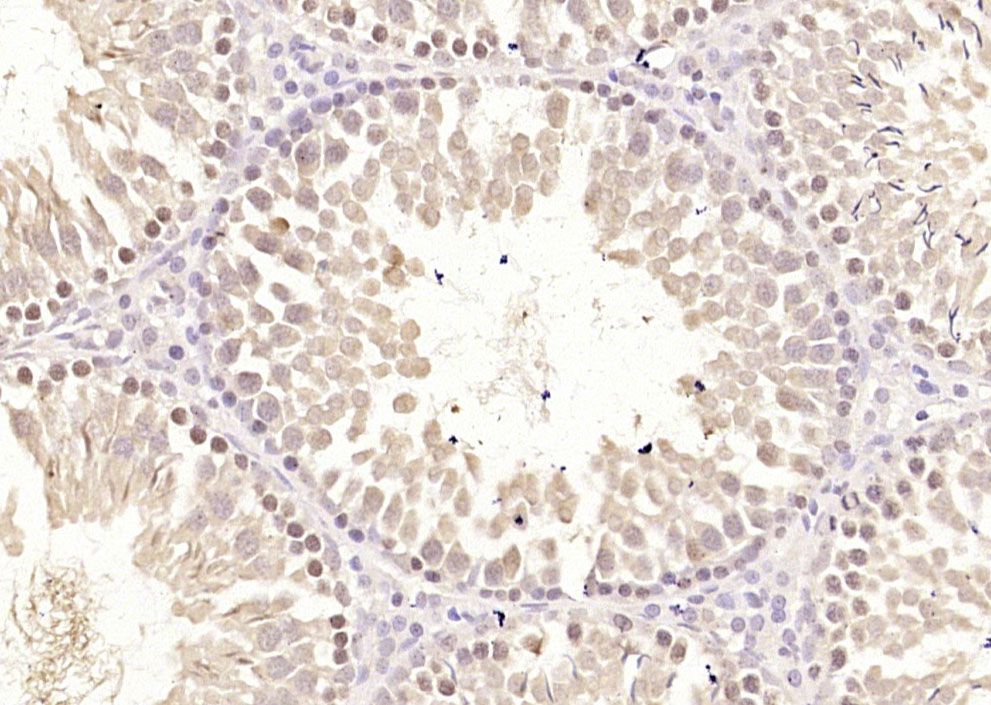

Paraformaldehyde-fixed, paraffin embedded (rat testis tissue); Antigen retrieval by boiling in sodium citrate buffer (pH6.0) for 15min; Block endogenous peroxidase by 3% hydrogen peroxide for 20 minutes; Blocking buffer (normal goat serum) at 37°C for 30min; Antibody incubation with (ECT2) Polyclonal Antibody, Unconjugated (bs-23904R) at 1:400 overnight at 4°C, followed by operating according to SP Kit(Rabbit) (sp-0023) instructionsand DAB staining.